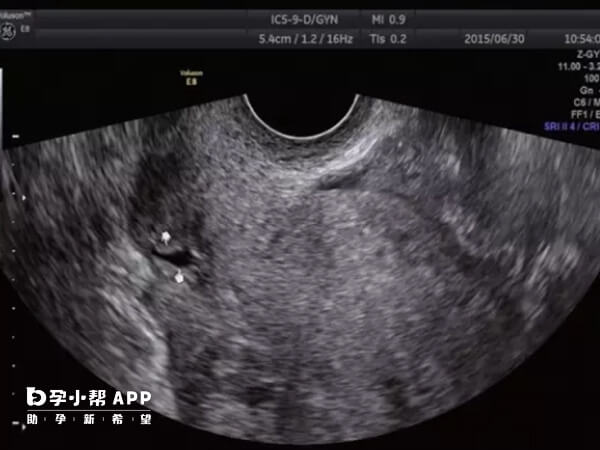

胸腔积液主要影响呼吸功能和身体舒适度,而胚胎着床主要取决于子宫内膜环境、胚胎质量、激素水平等因素。少量胸腔积液(如积液量<5mm)通常不会干扰胚胎在子宫内的着床过程。

若胸腔积液量较大或伴有严重腹胀、腹痛、呼吸困难等症状,可能提示OHSS进展,此时身体的应激状态可能影响激素平衡和子宫内环境,间接影响胚胎着床。